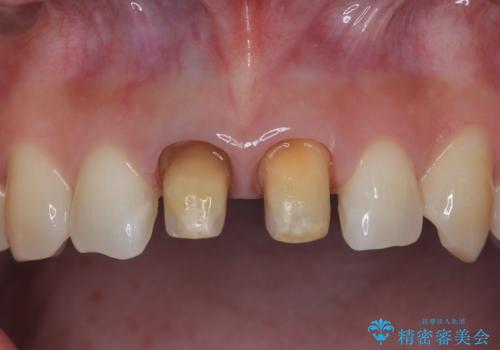

セラミッククラウンで前歯の変色を改善

- 前歯の変色が気になるというご相談をいただき、セラミッククラウンによる治療を行いました。

セラミッククラウンによって前歯の変色が改善され、また歯の形も希望の形態へ修正しました。